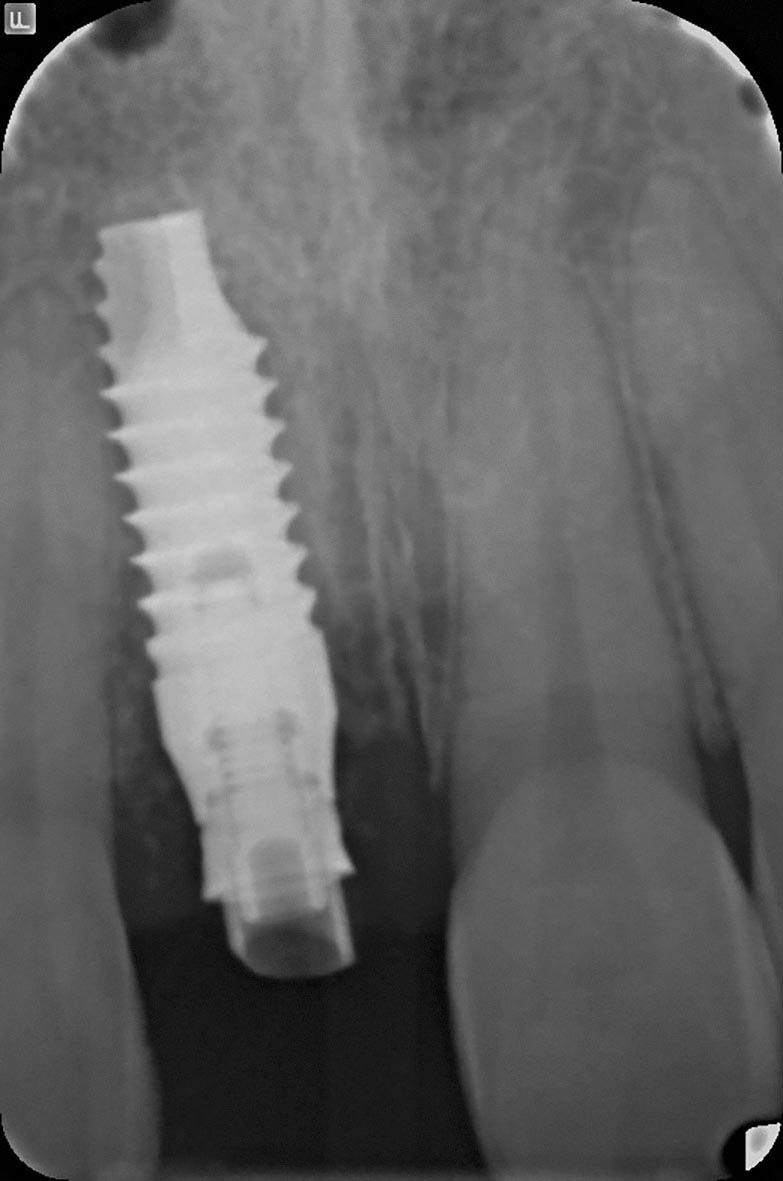

Radiographic control after surgery.